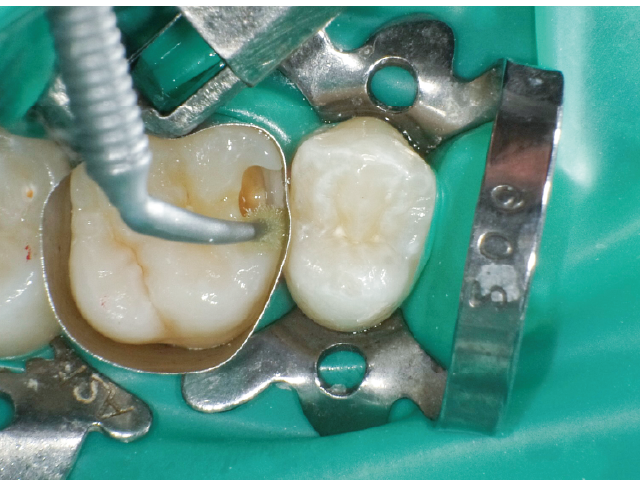

本症例では、ダイヤモンドの微粒子でコーティングされたエアースケーラーチップを窩洞形態の仕上げに使用。隣在歯の誤切削を防止し、エナメル質の切削断面を歯肉側窩縁までなめらかになるよう仕上げました。

本チップは切削時にストレスが少ない穏やかな振動のエアースケーラー専用のダイヤモンドチップで、切削部となる半球形状の面にのみダイヤモンド砥粒がコーティングされており、背面平坦部は隣在歯を削らないよう平滑になっています(図8、9)。チップの屈曲角度は110°に設定され、窩洞へのアクセスが容易な形状となっています。S67D(アングルの外側)、S68D(アングルの内側)チップは半球状の切削部位が設定され、臼歯部の近遠心両側の窩洞形成に使用が可能です。本症例では、左上6近心隣接面部の窩洞であったため、アングルの外側に半球状の切削部位が設定されている「S67D」を使用しました。これらの器具を使用することにより、頬舌側の隅角部歯質を温存した最小限の規模で窩洞形成を終了、防湿操作および隔壁の設置に移行することができました。

本症例では窩洞底部のエナメル質窩縁への窩洞形成の最終仕上げに硬組織の繊細な切削が可能なエアースケーラーチップを活用し不用意な窩洞規模の拡大を防ぐことができました。それにより、シンプルなマトリックスシステムでの隣接面部への精密な充填操作が可能となり、修復の長期予後に期待がもてる状況となりました。精度の高いMIコンポジットレジン修復において、エアースケーラー専用のダイヤモンドチップが非常に相性が良いことが確認されました。このような切削システムを有効に活用することで、より精密で長期的な修復結果が得られる可能性が高いと考えます。